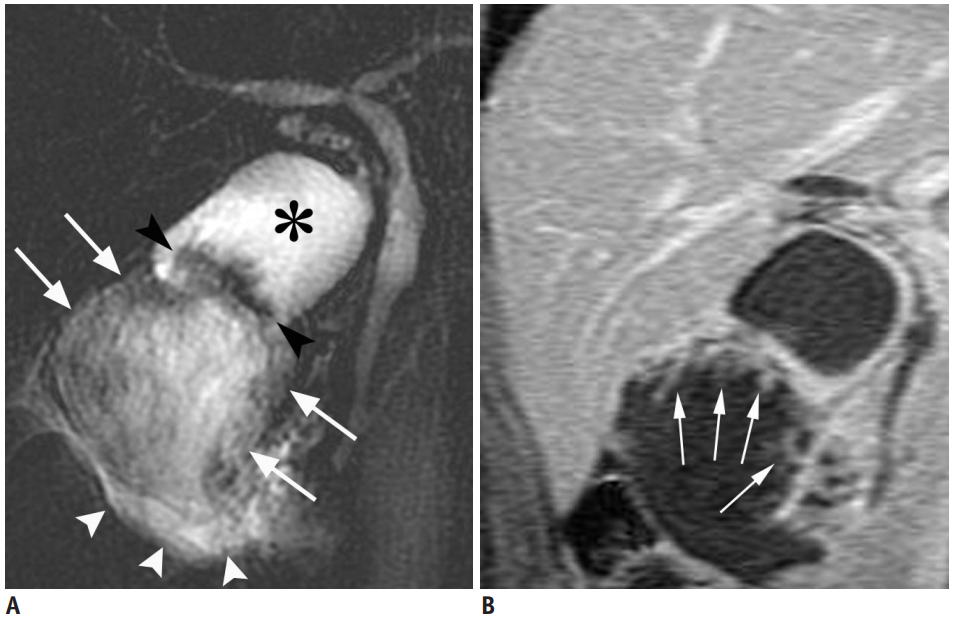

MRI can show a large, solid tumour that occupies or completely replaces the gallbladder; this is the most common imaging presentation and often indicates advanced disease. Such masses usually invade adjacent organs, particularly the liver, and may contain calcifications or gallstones within the tumour18,19,21,22.

Malignant thickening of the gallbladder wall on MRI typically appears as diffuse, nodular thickening with disrupted mucosal lines and absence of the normal layered appearance; apparent diffusion coefficient (ADC) values can help differentiate malignant from benign causes, with malignancy showing low ADC values and early contrast enhancement15,23,24.

MRI provides clear visualisation of local and advanced invasion, especially into the liver, using hepatobiliary contrast agents and dynamic scanning, often delivering higher sensitivity than other modalities; delayed enhancement in adjacent tissues can indicate hepatic involvement18,20,25.